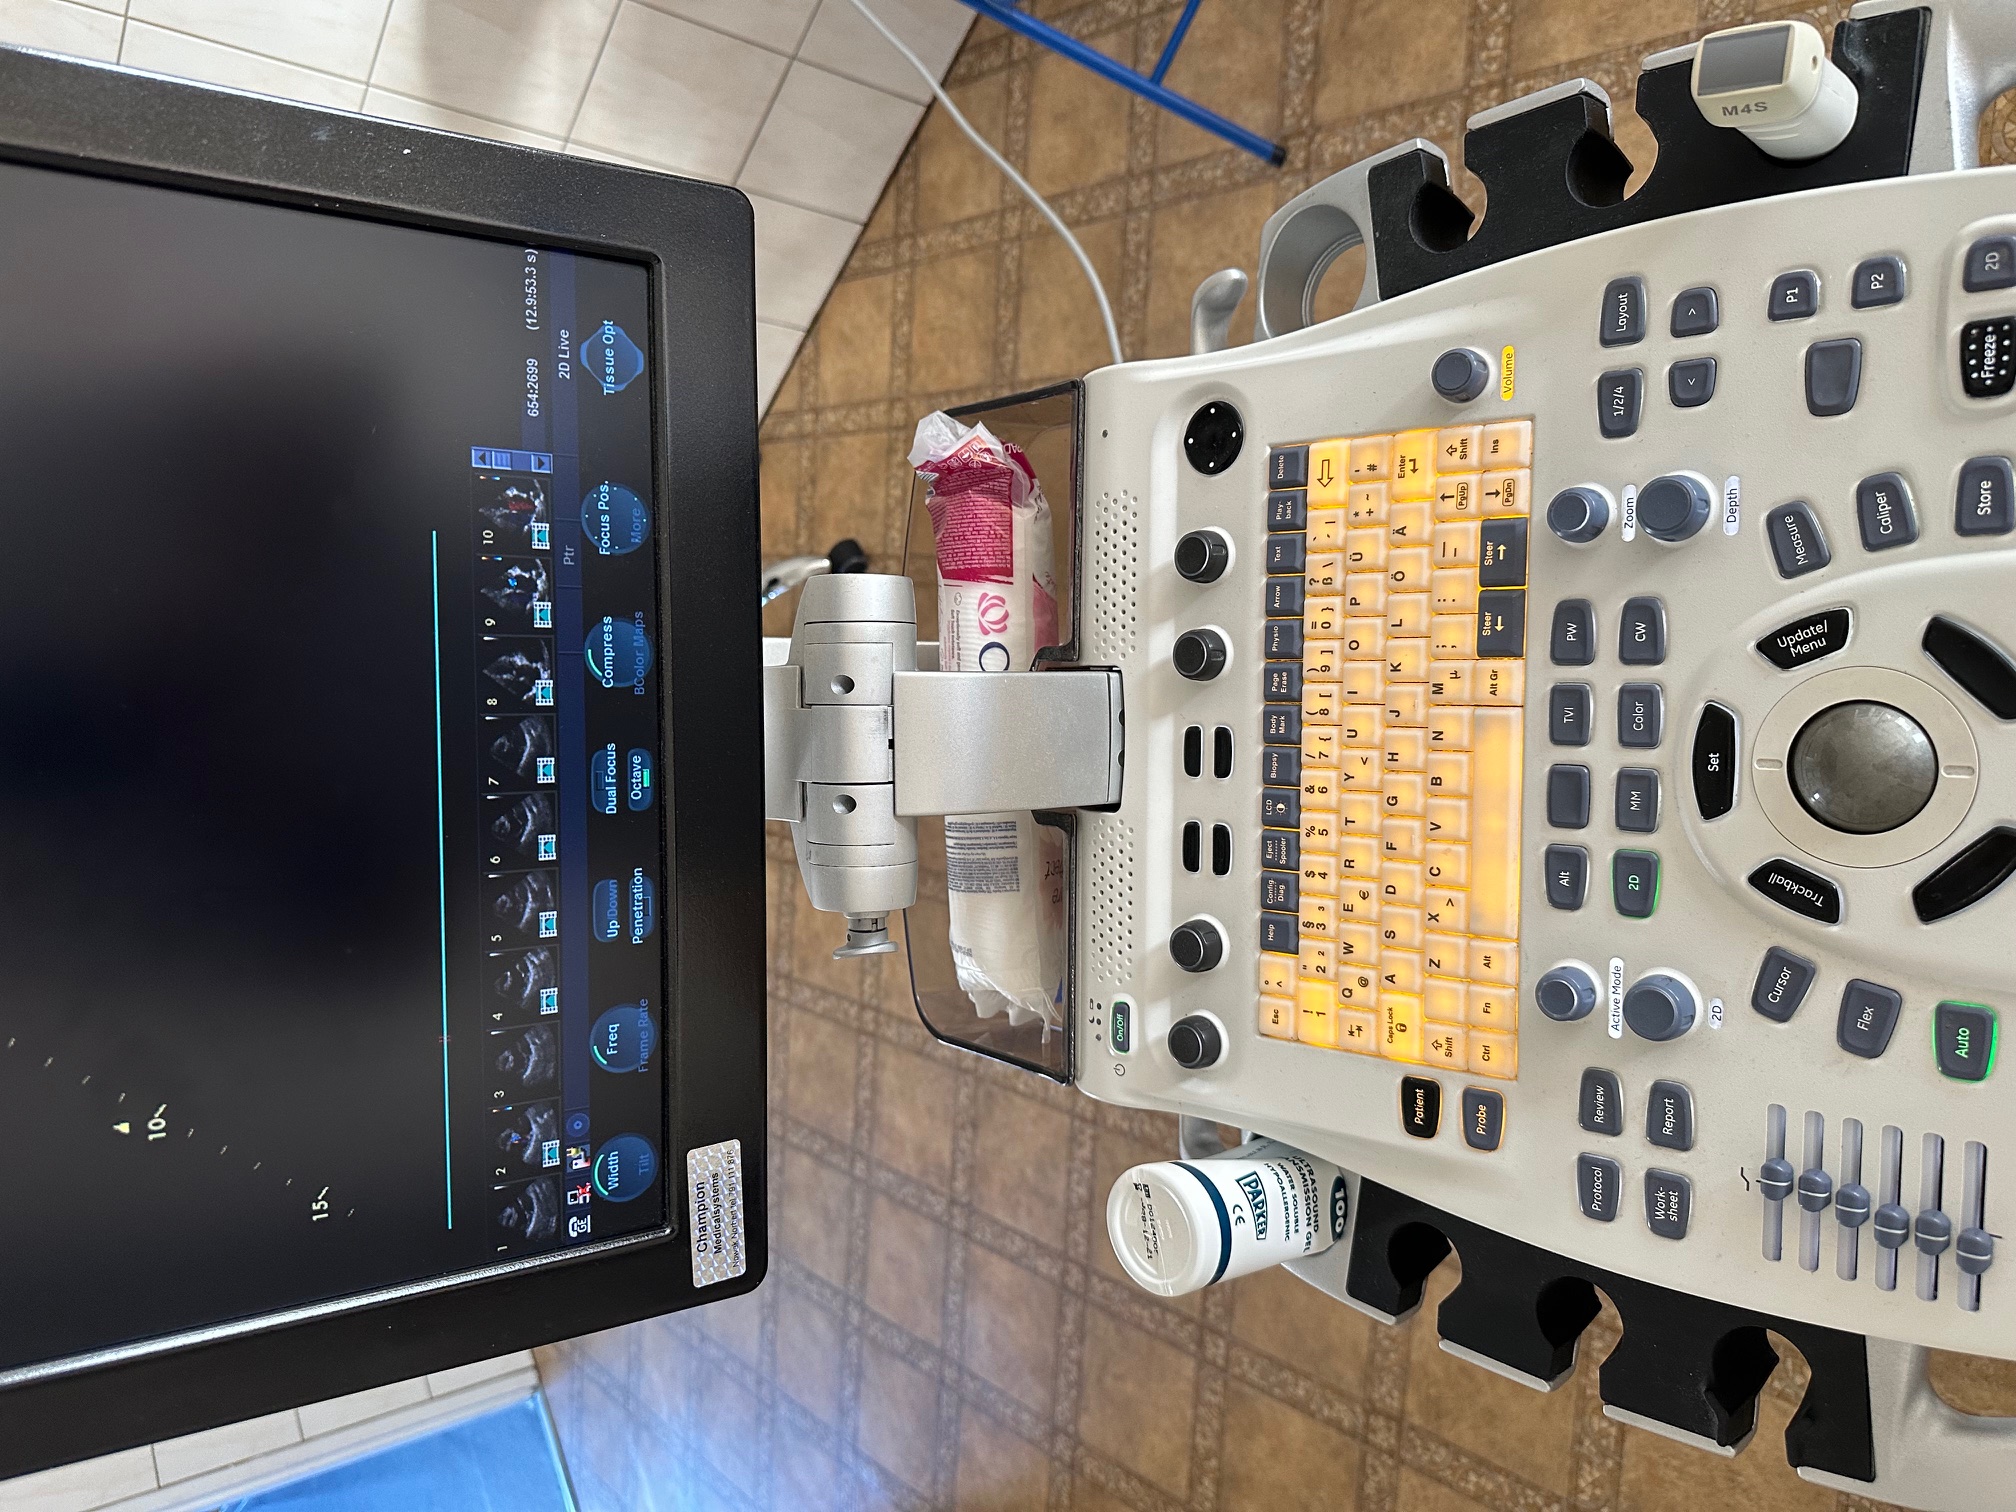

oferuję echokardiograf Vivid S6 z 2014r z głowicą M4S Rs z 2023r.

Aparat sprawny z aktualnym paszportem.

oferuję echokardiograf Vivid S6 z 2014r z głowicą M4S Rs z 2023r.

Aparat sprawny z aktualnym paszportem.